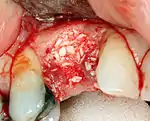

Additional procedures to augment deficient bone in implant site

For an implant to osseointegrate, it needs to be surrounded by a healthy quantity of bone. In order for it to survive long-term, it needs to have a thick healthy soft tissue (gingiva) envelope around it. It is common for either the bone or soft tissue to be so deficient that the surgeon needs to reconstruct it either before or during implant placement.[33]: 1084 All techniques of augmenting the alveolar bone in preparation for implant placement are invasive and associated with a degree of morbidity.[42]

Hard tissue (bone) reconstruction

Bone grafting is necessary when there is a lack of bone. Also, it helps to stabilize the implant by increasing survival of the implant and decreasing marginal bone level loss.[43] While there are always new implant types, such as short implants, and techniques to allow compromise, a general treatment goal is to have a minimum of 10 mm (0.39 in) in bone height, and 6 mm (0.24 in) in width. Alternatively, bone defects are graded from A to D (A=10+ mm of bone, B=7–9 mm, C=4–6 mm and D=0–3 mm) where an implant's likelihood of osseointegrating is related to the grade of bone.[44]: 250

To achieve an adequate width and height of bone, various bone grafting techniques have been developed. The most frequently used is called guided bone graft augmentation where a defect is filled with either natural (harvested or autograft) bone or allograft (donor bone or synthetic bone substitute), covered with a semi-permeable membrane and allowed to heal. During the healing phase, natural bone replaces the graft forming a new bony base for the implant.[39]: 223

Soft tissue (gingiva) reconstruction

The gingiva surrounding a tooth has a 2–3 mm band of bright pink, very strong attached mucosa, then a darker, larger area of unattached mucosa that folds into the cheeks. When replacing a tooth with an implant, a band of strong, attached gingiva is needed to keep the implant healthy in the long-term. This is especially important with implants because the blood supply is more precarious in the gingiva surrounding an implant, and is theoretically more susceptible to injury because of a longer attachment to the implant than on a tooth (a longer biologic width).[47]: 629–633

When an adequate band of attached tissue is absent, it can be recreated with a soft tissue graft. There are four methods that can be used to transplant soft tissue. A roll of tissue adjacent to an implant (referred to as a palatal roll) can be moved towards the lip (buccal), gingiva from the palate can be transplanted, deeper connective tissue from the palate can be transplanted or, when a larger piece of tissue is needed, a finger of tissue based on a blood vessel in the palate (called a vascularized interpositional periosteal-connective tissue (VIP-CT) flap) can be repositioned to the area.[41]: 113–188 Xenogeneic collagen matrices are used for gingival augmentation after dental implantation.[48][49]